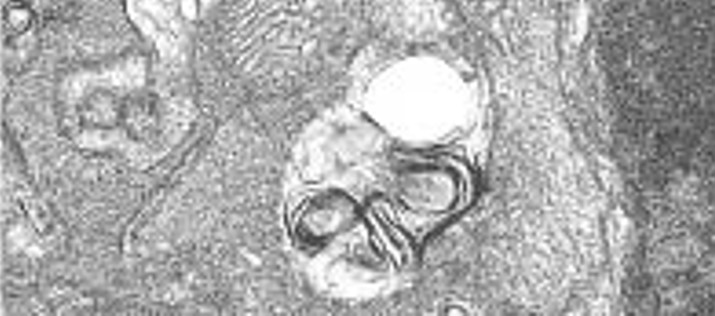

La falta de una única proteína acelera el envejecimiento muscular en ratones

22/06/2016